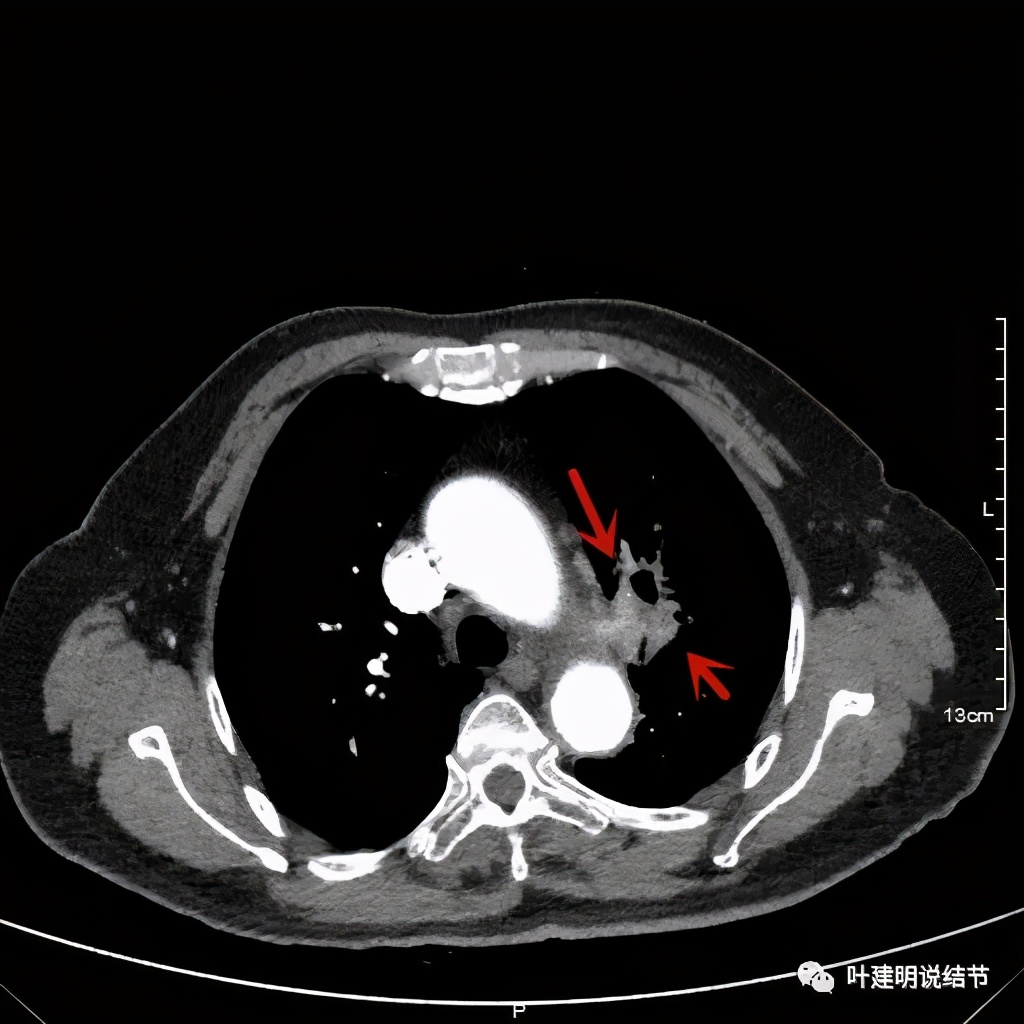

上图桔色箭头示左肺动脉分支处仍被软组织(原肿瘤所在)包绕,粉色箭头示肺动脉仍与肿瘤处关系密切

上图也示桔色箭头示左肺动脉分支处仍被软组织(原肿瘤所在)包绕,粉色箭头示肺动脉仍与肿瘤处关系密切

我样的治疗效果,显然超出了我们之前的预期,那么接下来拟选择行手术治疗,初定左上叶袖式肺叶切除加淋巴结清扫,但因为肺门区仍有软组织影,与肺动脉的关系仍密切,肿瘤与肺动脉间能否游离开来还是未知数,但至少得努力争取,鉴于患者年纪虽大,肺功能指标尚可,血气分析也基本正常,所以与患方沟通后确定行手术探查,但也也说明有万一全肺切除的可能(虽然这种可能性较小)。